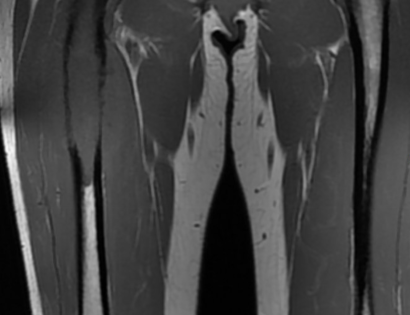

MRI photo of tumor

This is an MRI of the tumor located in the right femur (left side of the image). In comparison to the healthy bone on the left femur, there is a darkened tumor in the upper third of the right femur.